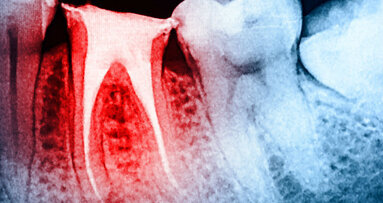

Rigenerazione del complesso polpa-dentina, gestione del dolore, procedimenti velocizzabili, soluzioni ricostruttive: è rappresentato tutto il percorso di ...